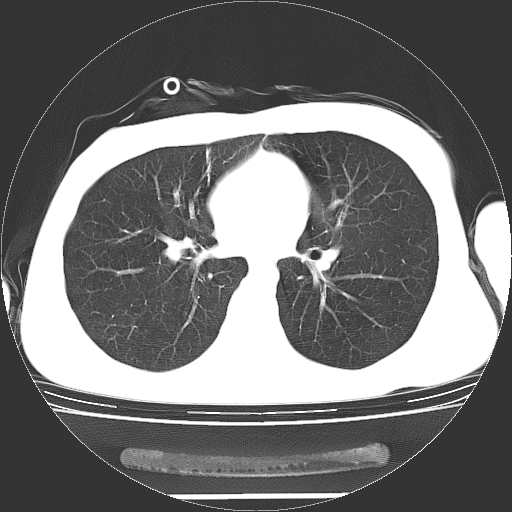

标题: CT19767:男,20岁,右侧气胸行闭式引流术后五天CT检查。 [打印本页]

男,20岁,右侧气胸行闭式引流术后五天ct检查看肺内是否有肺大泡,纵隔窗未见异常,未上传。

1)右侧胸腔闭式引流术后导管留置。2)右肺未见肺大泡。

未见肺大泡,还有微量气体。